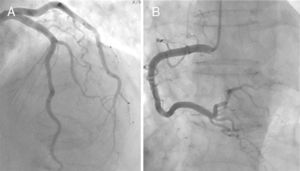

Echocardiography and ventriculography revealed akinesia/hypokinesia in all cases, in the apical (100%) and/or mid segments (90%), with impaired left ventricular ejection fraction (LVEF), ranging between 25% and 68% (Figure 1). Cardiac catheterization identified an intermediate lesion in the left anterior descending artery in one patient but no significant lesions in the others (Figure 3).

Diagnosis is confirmed by cardiac catheterization showing absence of or non-obstructive CAD.